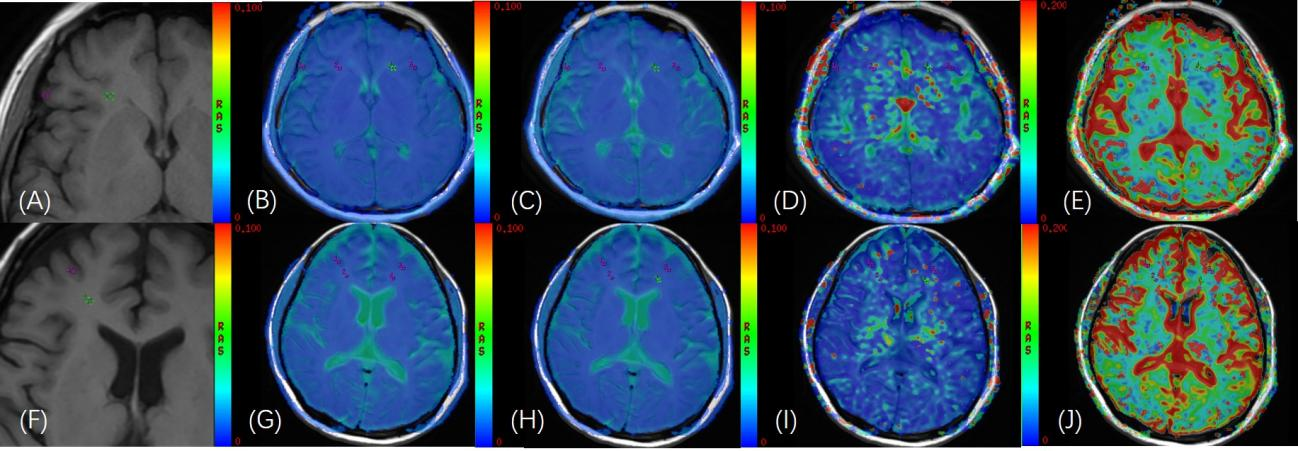

圖1:正常志愿者(A)頭顱軸位 T1WI 圖像;(B)-(E)在軸位 IVIM功能像(sADC、D、D*、f圖)與軸位 T1WI 融合圖像上勾畫雙側額葉的灰質、白質,(灰質:f =15.8%;白質:f =18.1%),ROI面積為8mm2。AL 患者(F)頭顱軸位 T1WI 圖像;(G)-(J)在軸位 IVIM 功能像(sADC、D、D*、f圖)與軸位 T1WI 融合圖像上勾畫雙側額葉的灰質、白質,(灰質:f =1.37%;白質:f =6.5%),ROI面積為8mm2。

研究表明,AL患者灰質和白質的血流灌注參數f值均顯著低于正常志愿者(z=-2.583,P =0.010;z=-2.923,P =0.003);腦組織灰質f值(7.08%)、白質f值(13.77%)是診斷AL的cutoff值。該研究結果首次發現AL患者腦血流灌注的異常。同時AL患者不同亞型大腦灰質和白質的D值不同,提示不同病理亞型AL腦組織微環境改變的異型性。